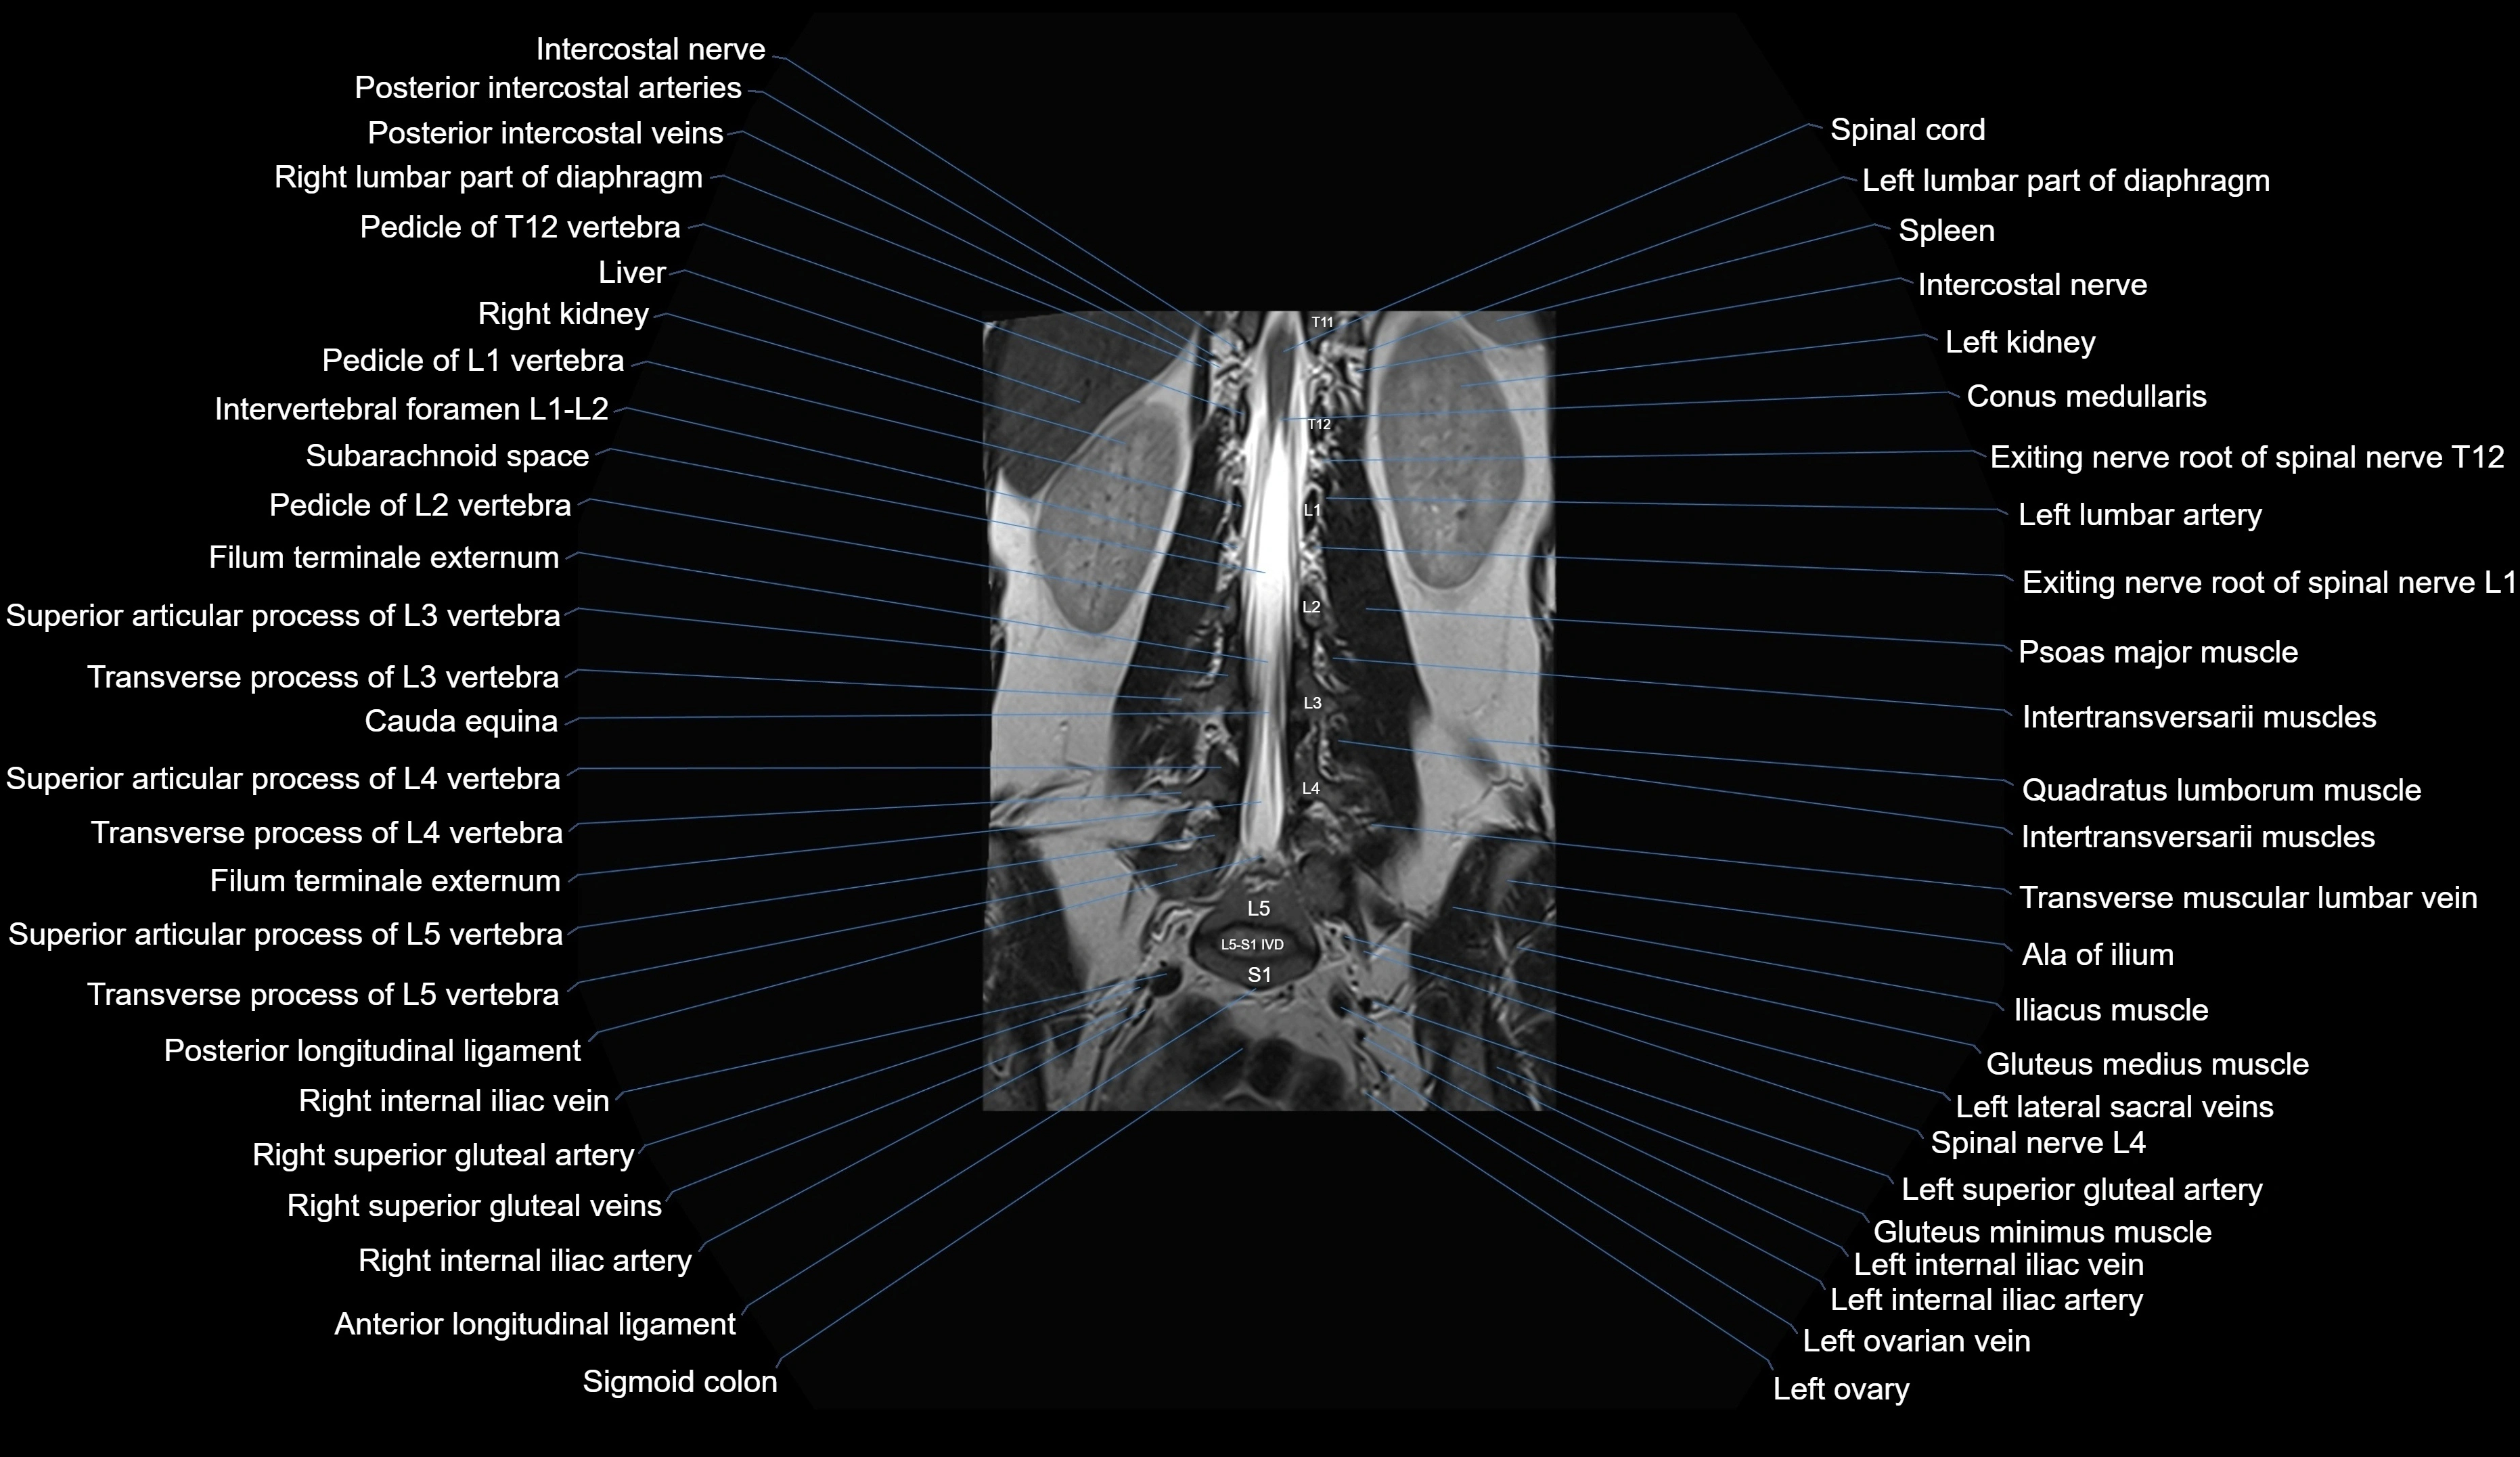

MRI images